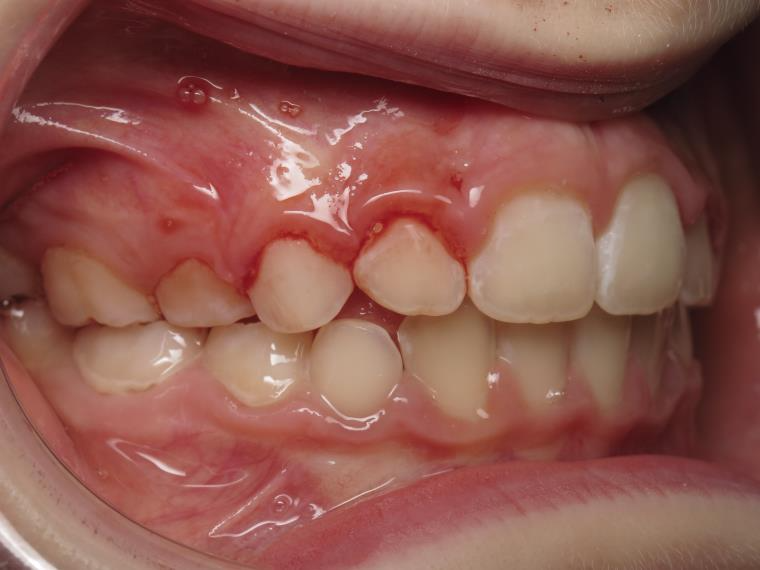

6 décalage sagittal 5 ans

Décalage entre les dents d avant en arrière

appareillage mobile